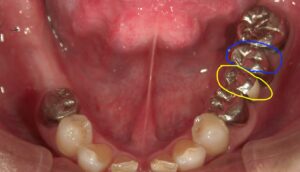

画像の様なイメージになります。針金を使いませんので

見た目がよくまた維持力も大きくとても良好な義歯となります。